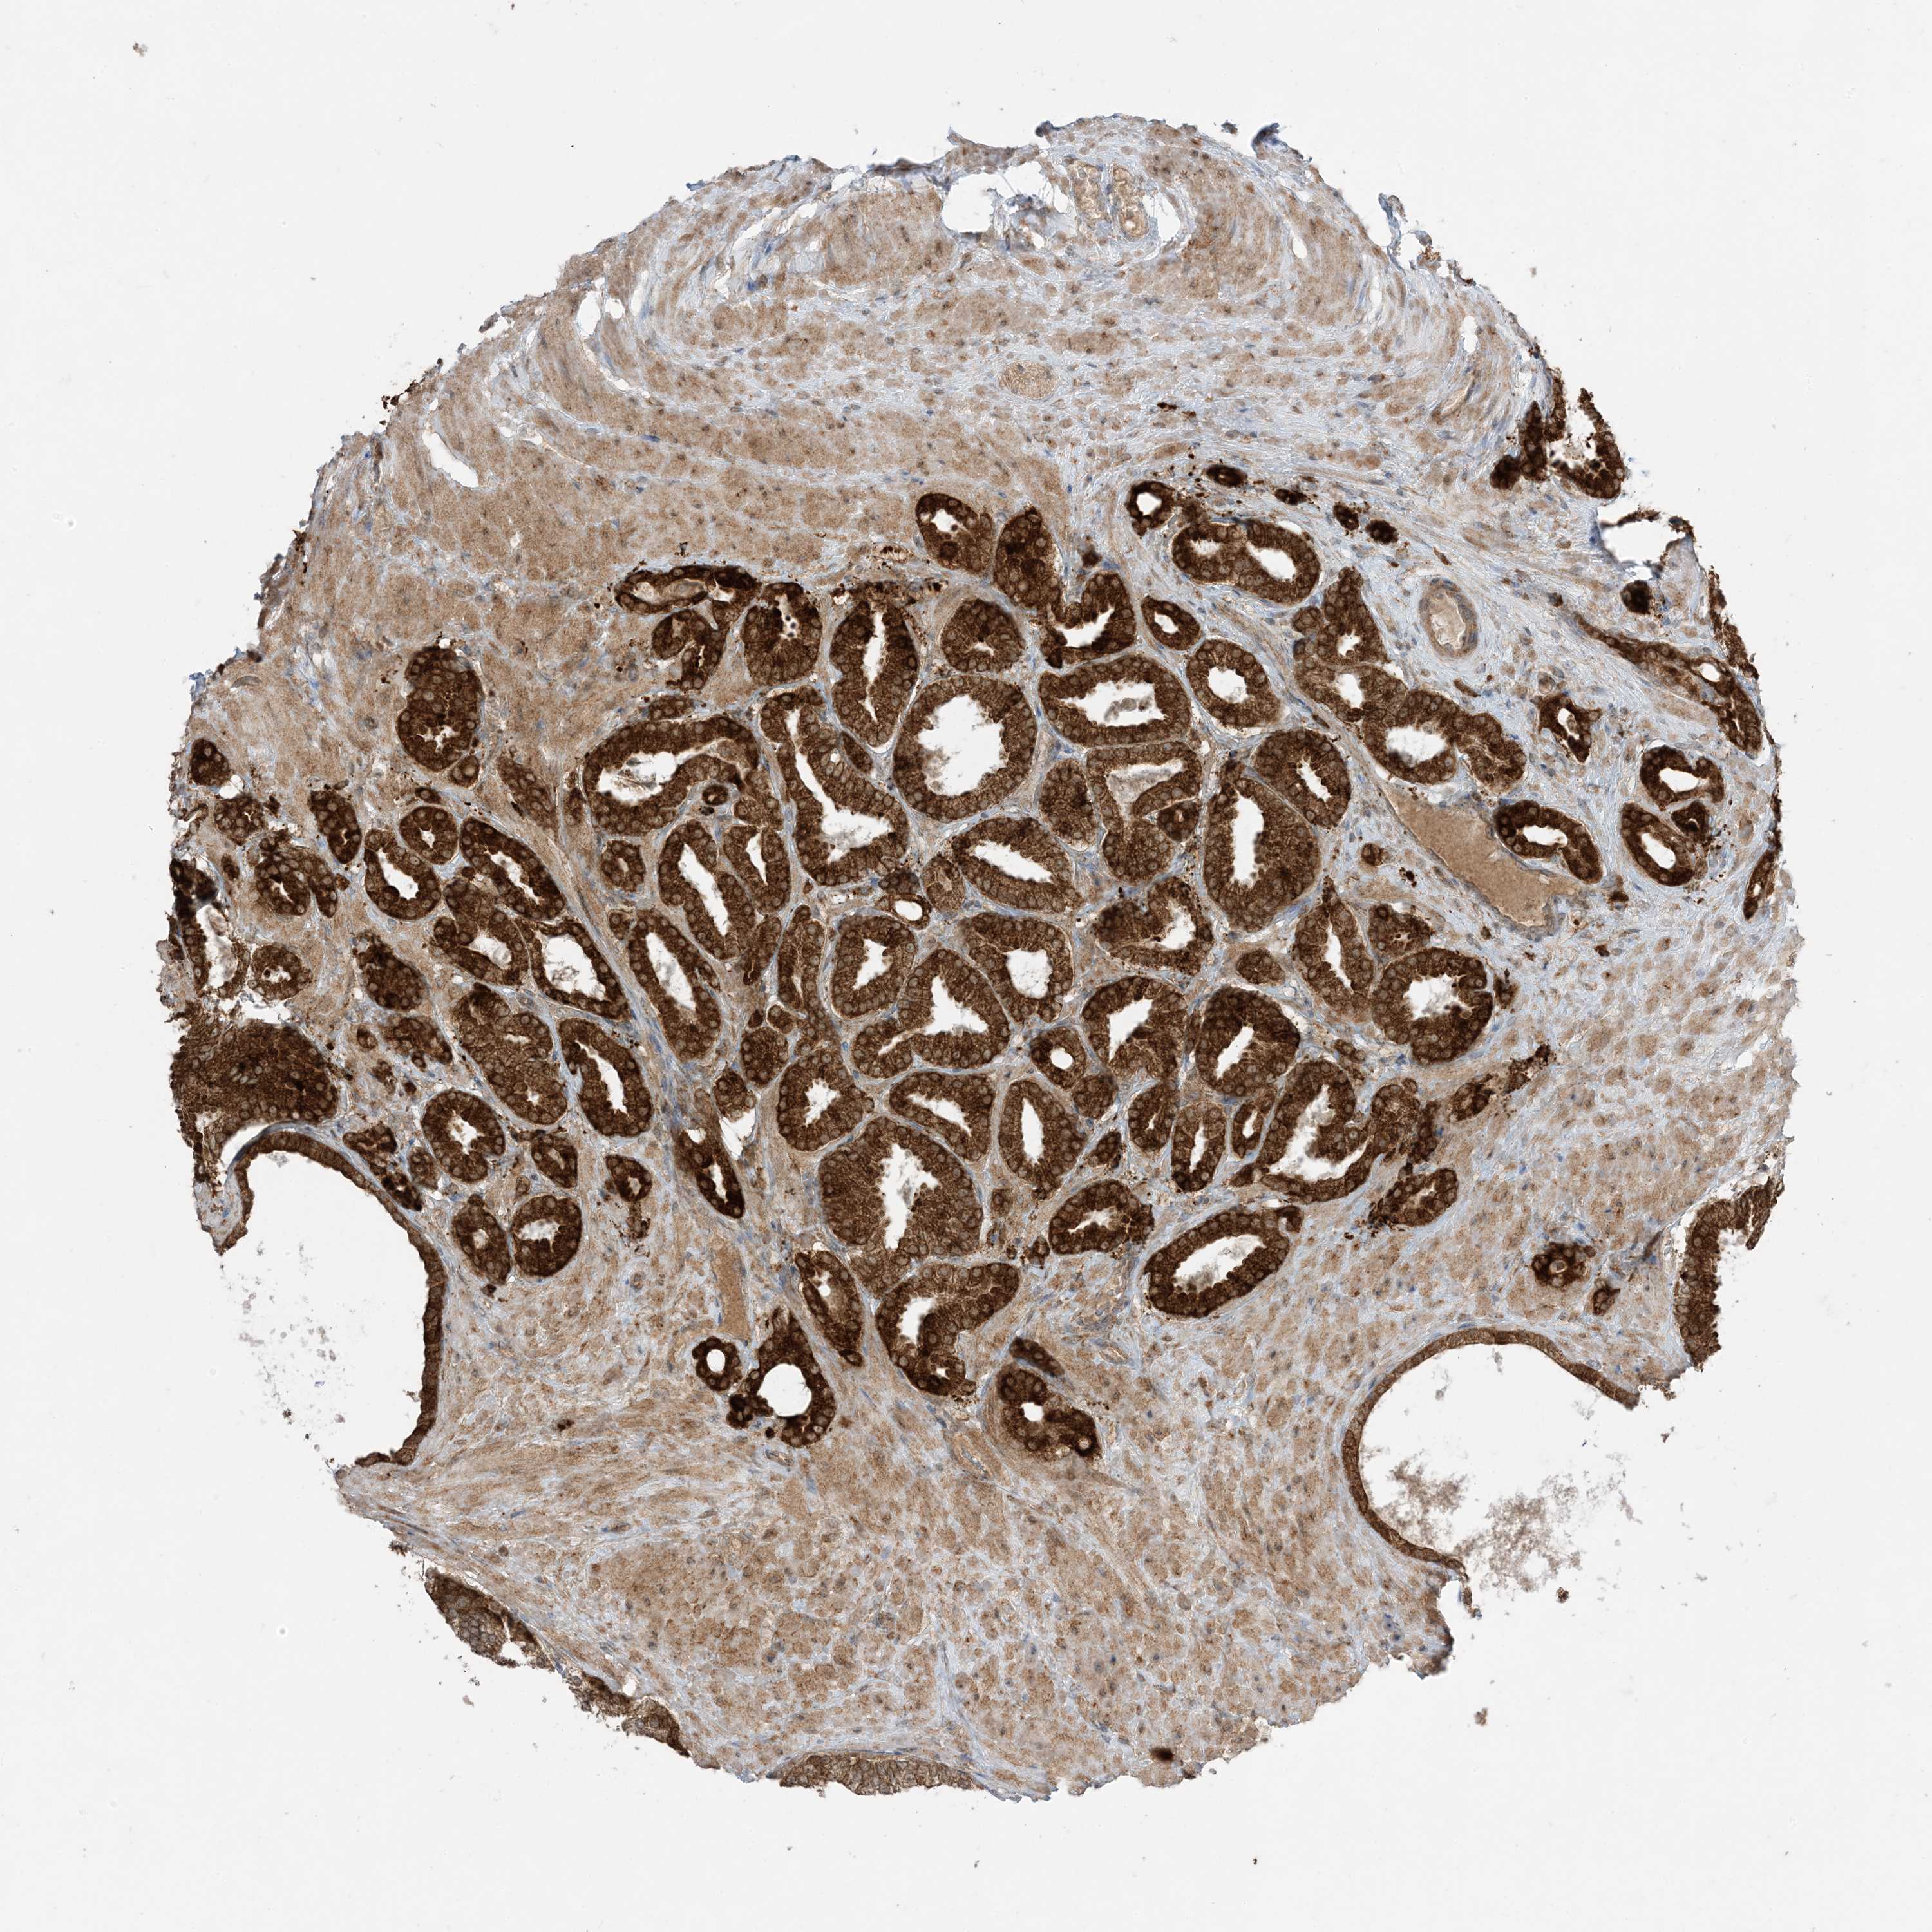

PROSTATE CANCER - Protein expressioni

A mouse-over function shows sample information and annotation data. Click on an image to view it in a full screen mode. Samples can be filtered based on level of antibody staining by selecting one or several of the following categories: high, medium, low and not detected. The assay and annotation is described here.

Antibody stainingi

Antibody staining in the annotated cell types in the current human tissue is reported as not detected, low, medium, or high, based on conventional immunohistochemistry profiling in selected tissues. This score is based on the combination of the staining intensity and fraction of stained cells.

Each image is clickable and will lead to virtual microscopy that enables deeper exploration of all samples and also displays staining intensity scores, fraction scores and subcellular localization as well as patient and tissue information for each sample.

Antibody HPA001536

Antibody CAB035996

Staining

High

Medium

Low

Not detected

Intensity

Strong

Moderate

Weak

Negative

Quantity

>75%

75%-25%

<25%

None

Location

Nuclear

Cytoplasmic/membranous

Cytoplasmic/membranous,nuclear

Adenocarcinoma, Medium grade

Adenocarcinoma, High grade

Adenocarcinoma, Low grade